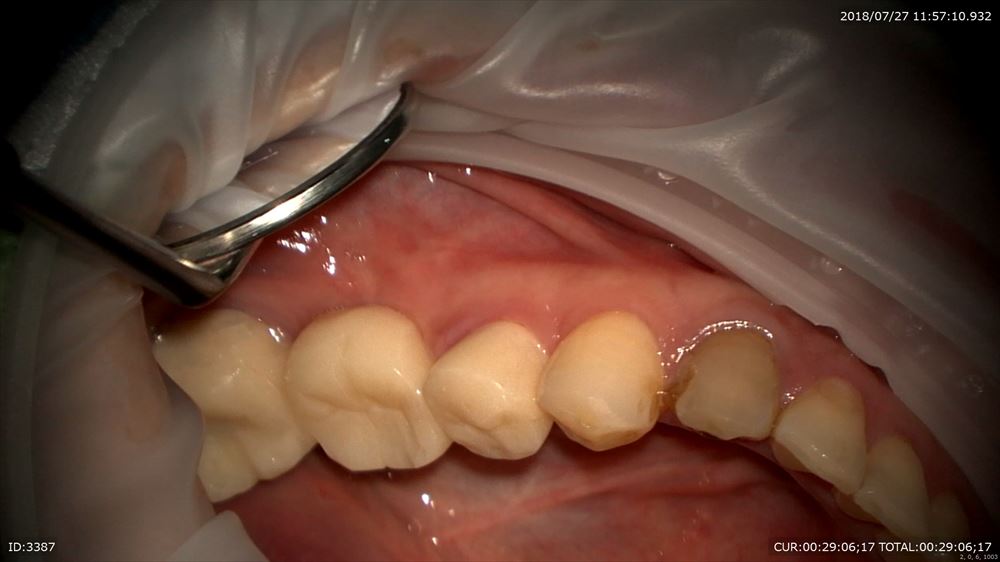

この様に仮歯で2ヶ月観察。問題なし。歯周病学会認定衛生士の歯周治療後私に昨日帰ってきました。

再発なしなので型とりへ

これは別の方

やる事は同じ。ブリッジであってもやる仕事はいつも同じ